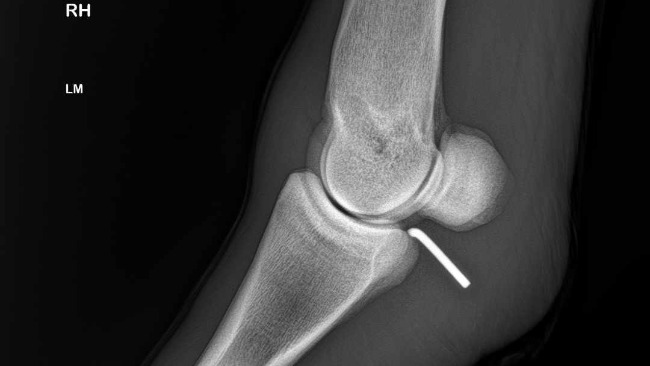

Około godziny 23:00 dotarliśmy na miejsce, gdzie zrobiono Rokiemu zdjęcia RTG nóżki i wtedy nastąpił szok: obce ciało (prawdopodobnie kawałek drutu) wbity w staw. Jak on się tam dostał? Nie mamy pojęcia. Decyzja: Młody zostaje w klinice, rano konsultacja z jej szefem, badanie stopnia zakażenia rany i tel do nas.